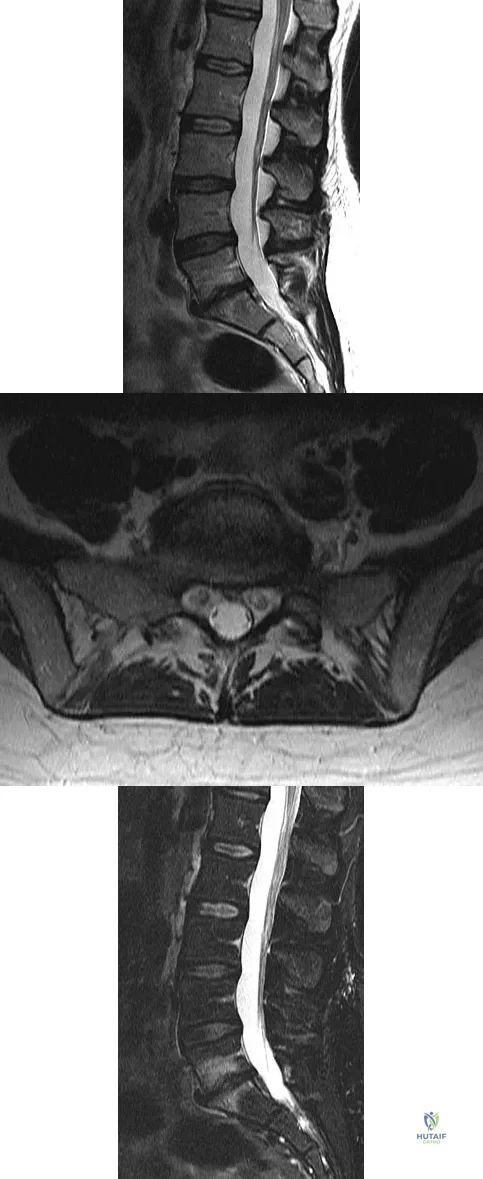

A 15-year-old girl who swims the breaststroke has had hip pain after training excessively for a national level competition. Based on the MRI scans shown in Figures 5a through 5c, what is the most likely diagnosis?

Explanation

Figures 11a and 11b show the T2-weighted MRI scans of the lumbar spine of a 53-year-old woman who has low back and right lower extremity pain. What structure is the arrow pointing to in Figure 11a?

Explanation

A 42-year-old woman who has had an 18-month history of severe low back pain is referred to your office for surgical evaluation. She reports that the pain initially began with right lower extremity pain and management consisted of oral analgesics, nonsteroidal anti-inflammatory drugs, and muscle relaxants. She has seen a chiropractor as well as a pain management specialist and she is status-post epidural steroid injections. She has also completed exhaustive physical therapy, as she is a certified athletic trainer and runs a health fitness program at a community hospital. Currently, she denies lower extremity pain and her pain is isolated to her low back and is subjectively graded as 8/10, with 10 being the worst pain she has ever experienced. The pain is interfering with her activities of daily living and she is seeking definitive treatment. Figures 32a through 32c show current MRI scans. Based on the current available medical literature, what is the most appropriate treatment?

Explanation